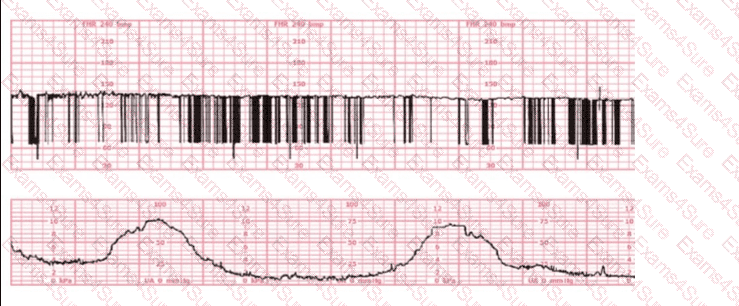

This fetal heart rate tracing is obtained upon the woman's admission to labor and delivery. This tracing is most reflective of: